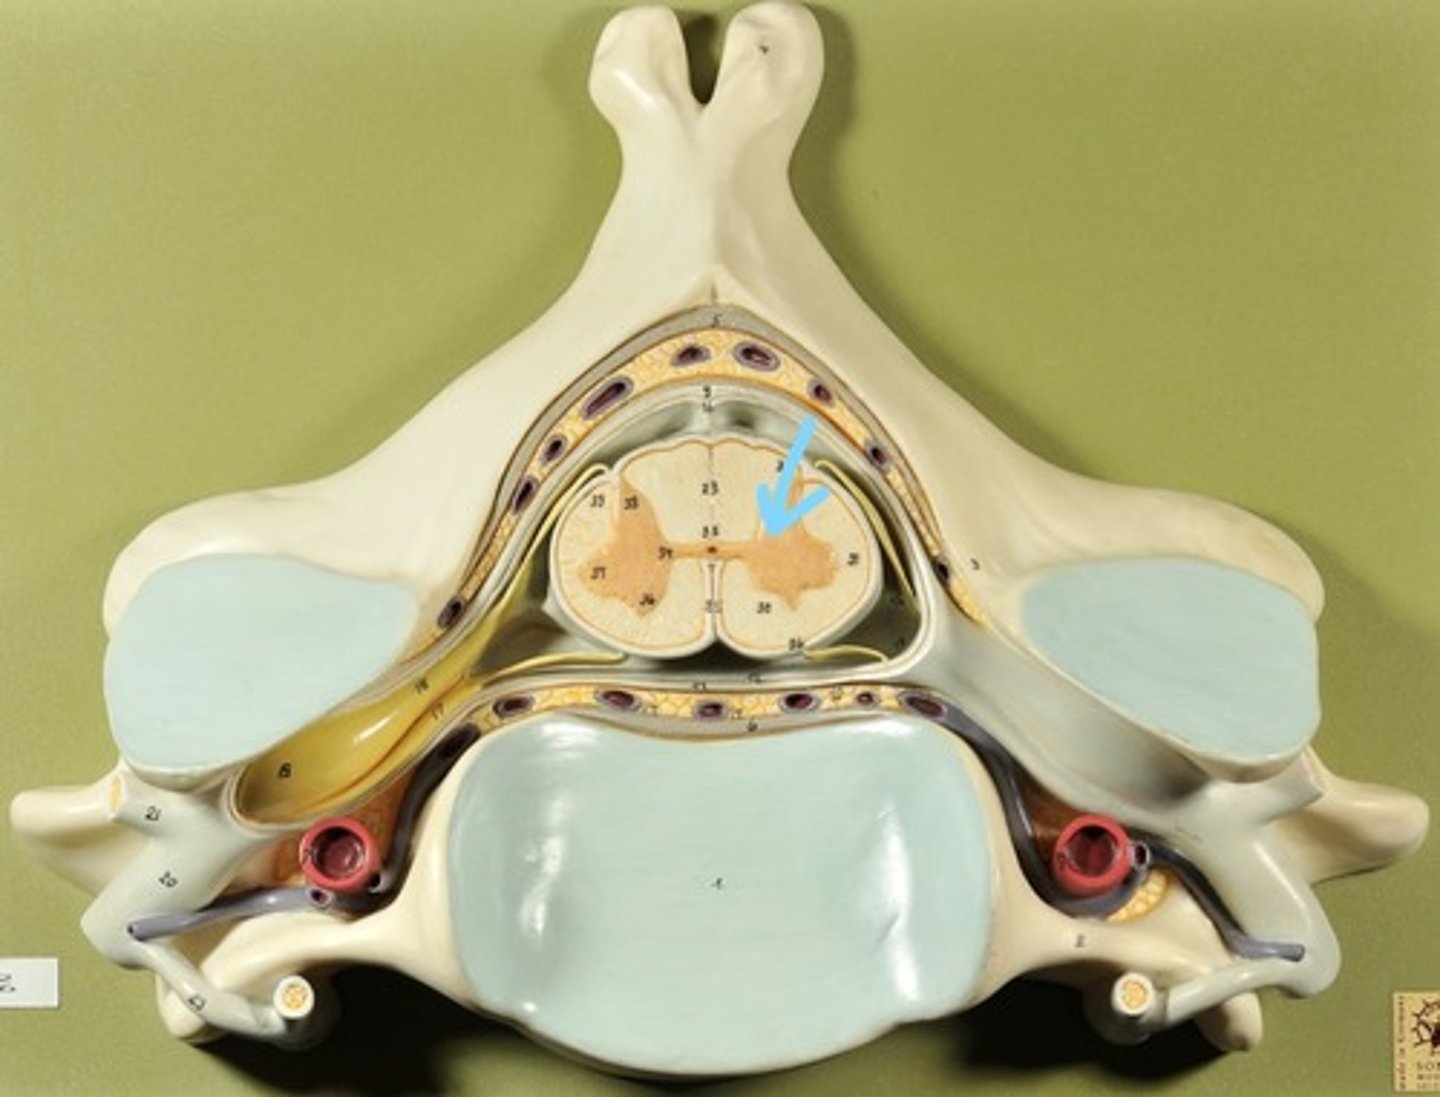

Identify all structures of spinal cord

White Matter of spinal cord

gray matter of spinal cord

Ventral Horns (gray matter)

Lateral Horns (gray matter)

Dorsal horns (gray matter)

Anterior Columns (white matter)

Lateral Columns (white matter)

Posterior Column (white matter)

central canal of spinal cord

Identify all structures

Pia Mater

Subarachnoid Space

Arachnoid mater

Subdural Space (brown line)

Dura mater

Epidural Space

Dorsal Root Ganglion

Dorsal Root

Ventral Root

Spinal Nerve